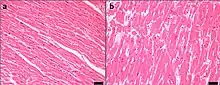

Within the heart, the working fibers of the myocardial tissue increase in size. As the heart works harder the actin and myosin filaments experience less overlap which increases the size of the myocardial fibers. If there is less overlap of the protein filaments within the sarcomeres of the muscle fibers, they will not be able to effectively pull on one another. If the heart tissue gets too big and stretches too far, then those filaments cannot effectively pull on one another to shorten the muscle fibers, impacting the heart's sliding filament mechanism. If fibers cannot shorten properly and the heart cannot contract properly, then blood cannot be effectively pumped to the lungs to be re-oxygenated or to the body to deliver oxygen to the working tissues of the body.